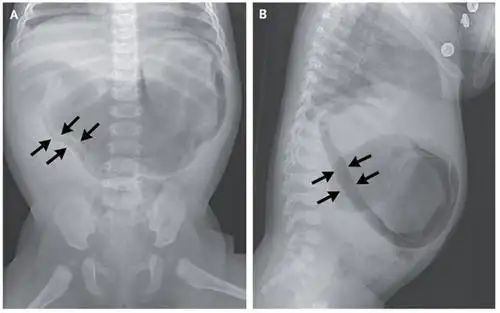

气腹造影原理 正常腹腔ct及肠粘连的表现

气腹征

疾病谱丨气腹

【急诊】卧位及立位腹平片——正常,气腹,小肠梗阻,前哨肠曲